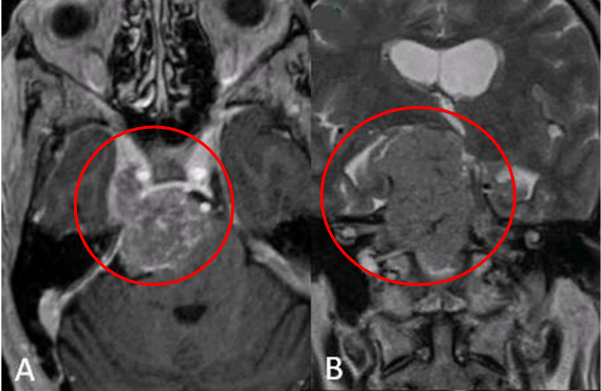

術(shù)前:A軸向增強(qiáng)和B矢狀t2加權(quán)MRI顯示右側(cè)大巖斜坡腦膜瘤伴幕上成分,腦干受壓,累及Meckel洞和右側(cè)海綿竇。

術(shù)后:C術(shù)后軸位及D冠狀位T2加權(quán)磁共振成像(MRI)顯示,腫瘤已實現(xiàn)大體切除,同時觀察到神經(jīng)血管結(jié)構(gòu)得到有效減壓。